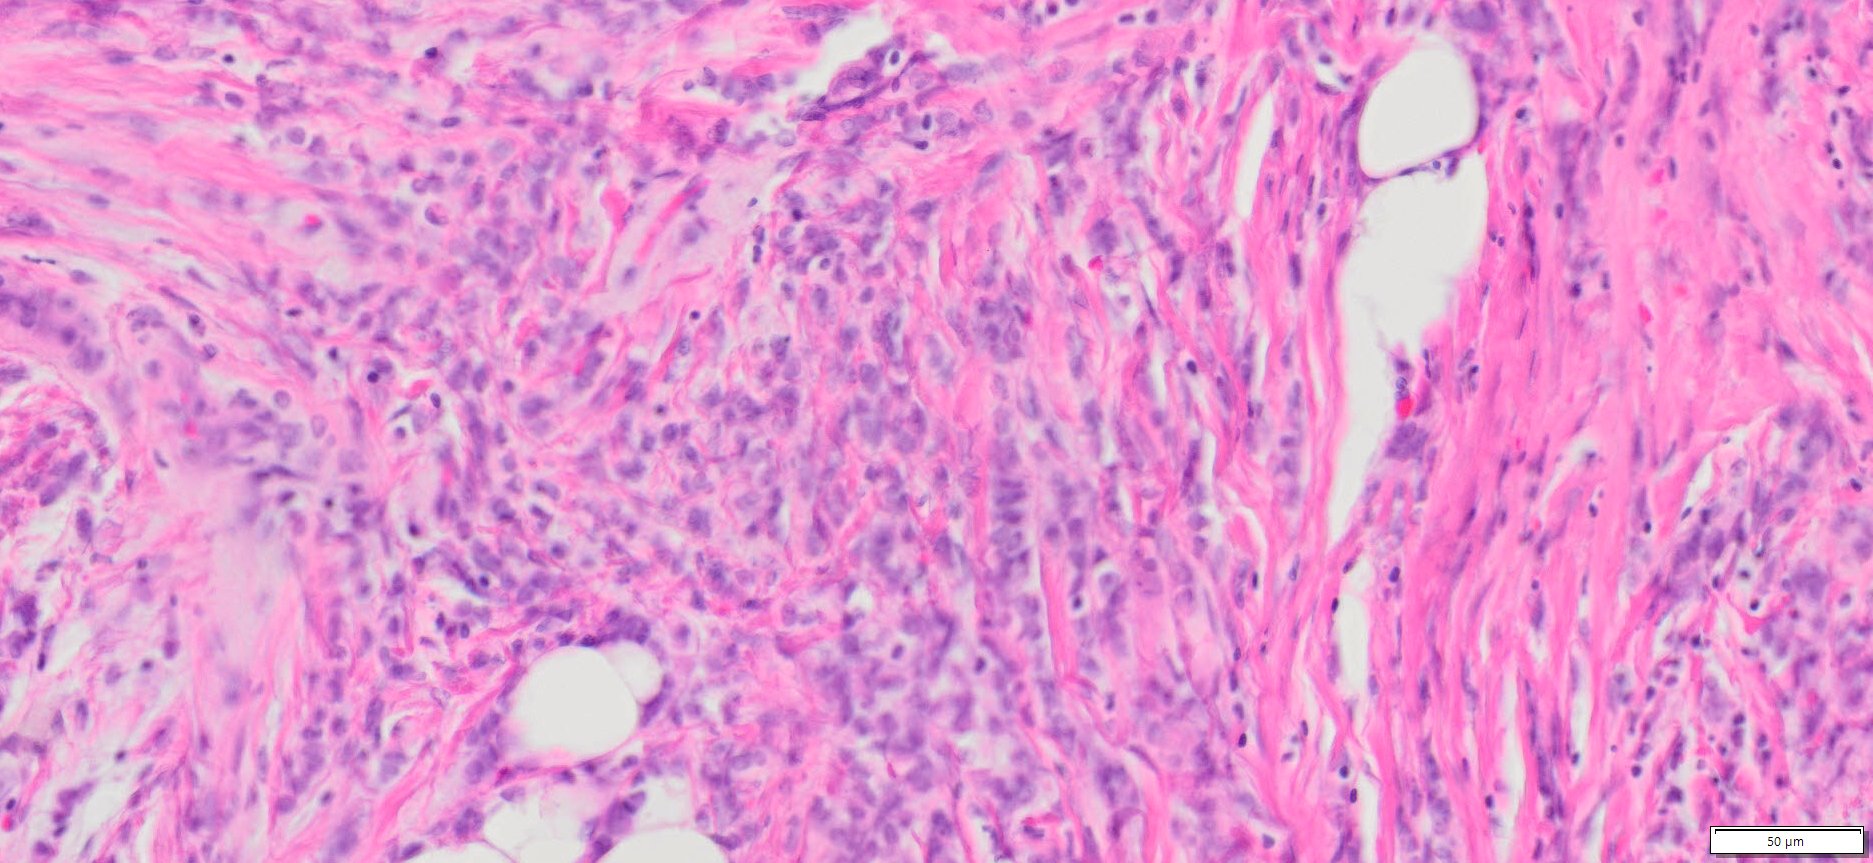

| HuPS-02033T1 | Breast | Invasive lobular carcinoma | No | Female/56 | 45% | II | pT3pN2aMx | NA |

Human tissue was fixed in formalin immediately after excision and embedded in paraffin. The tissue sections were 5 µm in thickness and mounted each on positively charged glass slides.